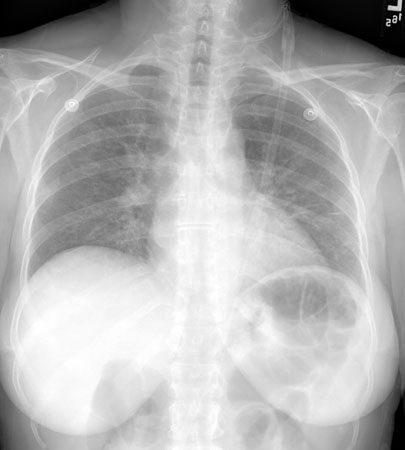

Pneumocystis jirovecii pneumonia

Posteroanterior chest x-ray showing mild, reticular, bilateral pulmonary interstitial infiltrates

From the collection of Matthew Gingo, UPMC